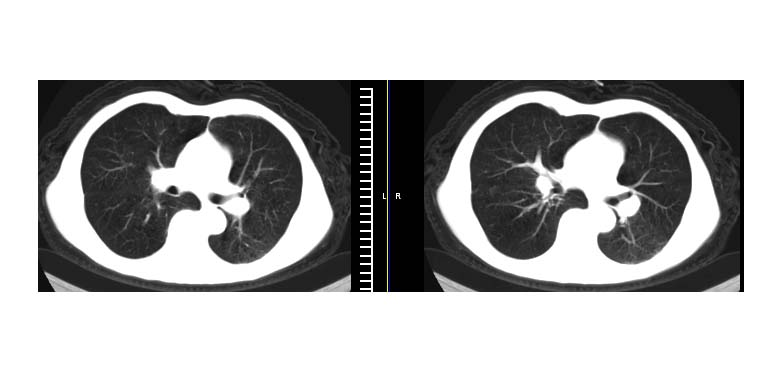

标题: CT11019:男性,66岁。发烧5-6天。治疗后无明显好转。 [打印本页]

标题: CT11019:男性,66岁。发烧5-6天。治疗后无明显好转。

左下肺中央型肺癌伴阻塞性肺炎\\肺不张可能性大,建议支纤镜检查.

左下肺中心性肺癌伴下肺不张及周围阻塞性炎症

左下肺中央型肺癌伴阻塞性肺炎\\肺不张可能性大,建议支纤镜检查

左侧胸廓偏小,左下梭形高密度影,考虑阻塞性肺炎.

左肺门下分增大见有结节影,基底干及分支显示不清,下叶体积缩小,呈片带状机磨玻璃样影显示。支持考虑左下肺中心型肺癌伴阻塞性肺炎及部分肺不张。建议纤支镜检查

明明是斜裂胸膜积液,为何都考虑阻塞性肺炎、肺不张(边缘内凹,而本例是外凸)。